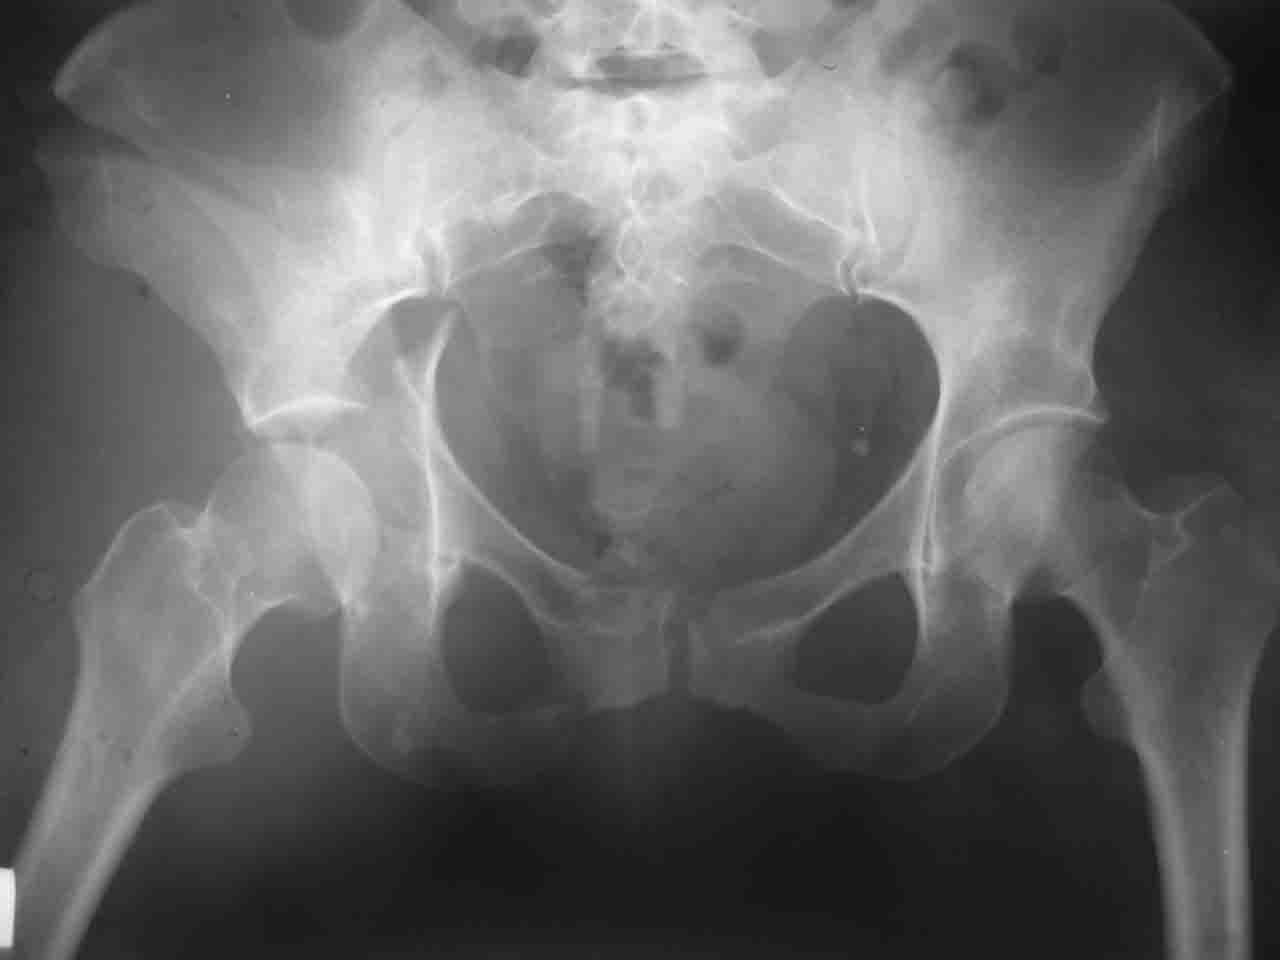

Уважаемые коллеги,43 летний мужчина, попав в автоаварию 13.10.2004, получил оскольчатый перелом обеих колонн левой вертлужной впадины.

На рентгенограммах - высокий двухколонный перелом вертлужной впадины с нарушением конгруэнтности, имеется обратная клиновидность суставной щели.

Спасибо за комментарии и рекомендации. Откровенно говоря, больного я прооперировал на прошлой неделе, через 5 дней после аварии и проблем с ним пока никаких нет, на удивление при достаточно обширной диссекции (илиофеморальный доступ) болей практически нет, так что больной самостоятельно садится в кровати, выполняет активные движения в оперированном суставе, сгибая до 60 градусов пока, далее с ассистенцией.

Причиной обращения к сообществу были возникшие непосредственно после операции сомнения и разочарования полученным качеством репозиции: а надо ли было трогать перелом вообще, репозиция передней колонны технически была очень сложна для меня, хотя реконструкции была в той же последовательности, что Д-р А.В.Рунков рекомендовал, в какой-то момент безуспешных манипуляций стал думать о *вторичной конгруэнтности*, которую не так давно обсуждали на

форуме и скелетном вытяжении. С репозицией и фиксацией задней колонны и отдельно задне-верхней стенки впадины проблем не возникло. Послеоп. Рг граммы в приложении. Если возникнут какие-либо дополнения или поправки - был бы признателен.